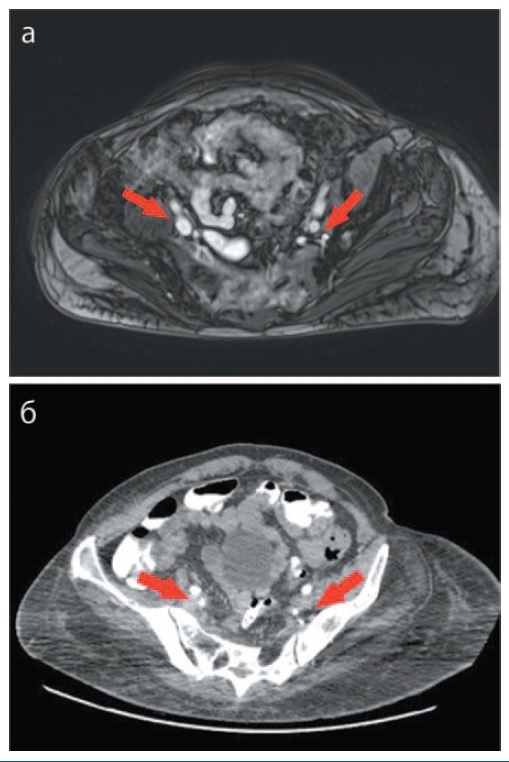

После 18 введений пембролизумаба по данным КТ органов брюшной полости отмечаются уменьшение размеров подвздошных лимфатических узлов справа до 11×15 мм (ранее 19×13 мм), слева до 8 мм (ранее – 17×14 мм), уменьшение размеров инфильтрата правой седалищной области до 39×57 мм (ранее 50×61 мм); рис. 2. Таким образом, у пациентки достигнут частичный регресс. При физикальном осмотре пролежень активно эпителизируется со значимым уменьшением в объеме и глубине с минимальным серозным отделяемым (рис. 3).

Рис. 2. МРТ органов малого таза: а – до начала иммунотерапии; б – на фоне 18 введений. / Fig. 2. Magnetic resonance imagining of the pelvis: a – before the beginning of immunotherapy; b – after 18 infusions.